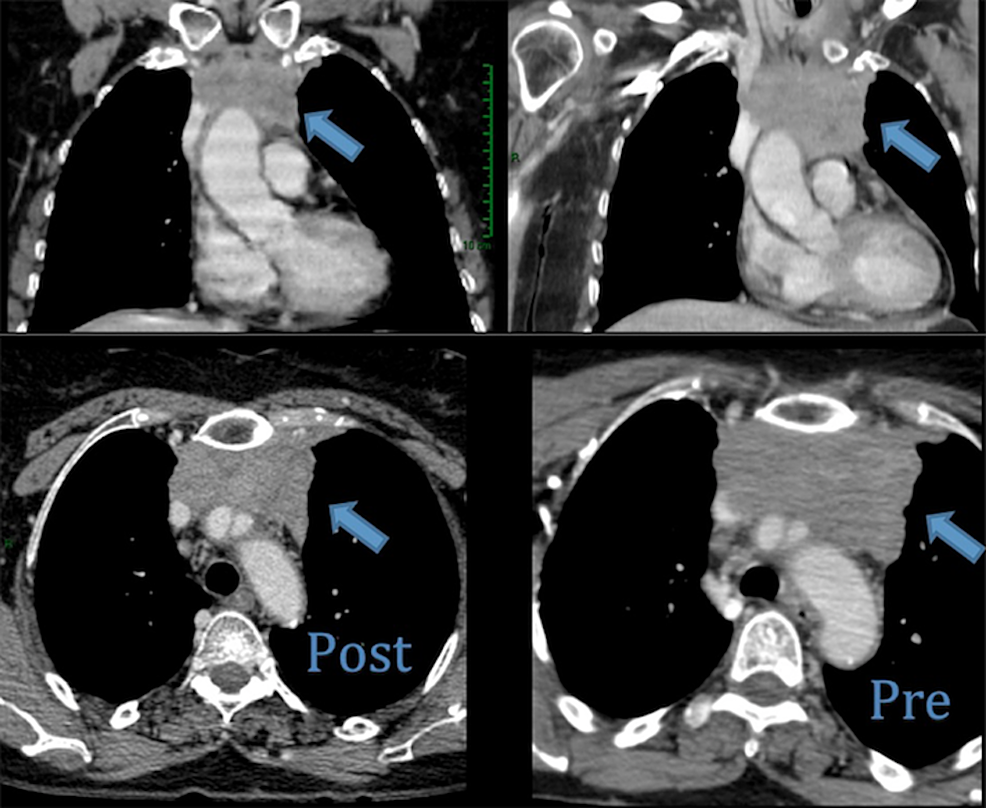

Image series of metastatic thymic carcinoma. a Coronal PET CT showing Thymic Carcinoma Lung Metastasis lung cancer ranks second position in incidence and the first in mortality among all cancers 1. all tets have malignant potential and the ability to metastasize. the clinical presentation, diagnosis, staging, and management of thymoma and thymic carcinoma are. the latest world health organization (who) classification from 2015 has grouped lung and thymic neuroendocrine tumours (nets). Thymic Carcinoma Lung Metastasis.